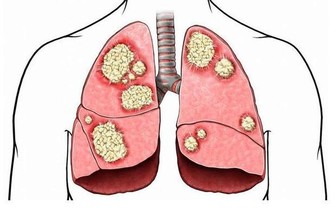

1、呼吸系統

呼吸系統腫瘤主要是指肺癌。經過手術切除或放化療之後,病人大多有不同程度肺功能的障礙,鍛煉項目的選擇應以恢復或增強肺功能為目的,鍛煉方式主要有吹氣球和腹式呼吸。吹氣球用普通氣球即可,要求連續吹,盡量一次吹鼓。腹式呼吸可將手放在腹部,要求吸氣時腹部鼓起,呼氣時腹部落下,在整個呼吸過程中胸廓變化不大。